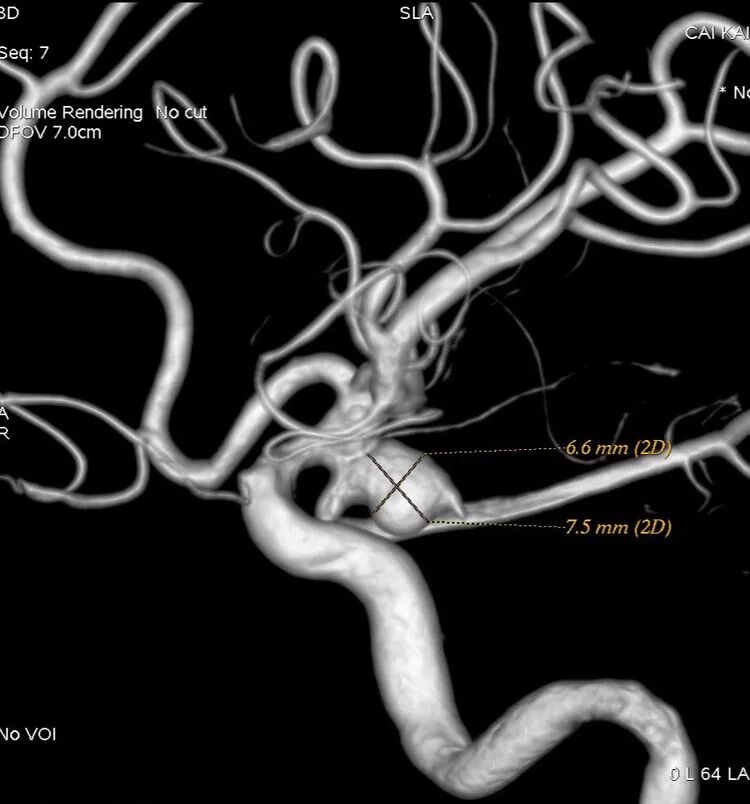

我们来看看动脉瘤的结构:红色为颈内动脉走向,绿色为后交通动脉走向,蓝色为动脉瘤

栓塞的要点,既要致密填塞,又要保证颈内动脉和后交通动脉的通畅。决定通过对侧前交通动脉-颈内动脉远端-后交通动脉途径来置入输送支架的微导管,从后交通动脉释放支架直到颈内动脉末端,以达到一个支架对颈内动脉和后交通动脉的保护

男,49岁,蛛网膜下腔出血

左侧后交通动脉瘤,胚胎型大脑后动脉

3D

局部观,宽颈,涉及颈内动脉和后交通动脉